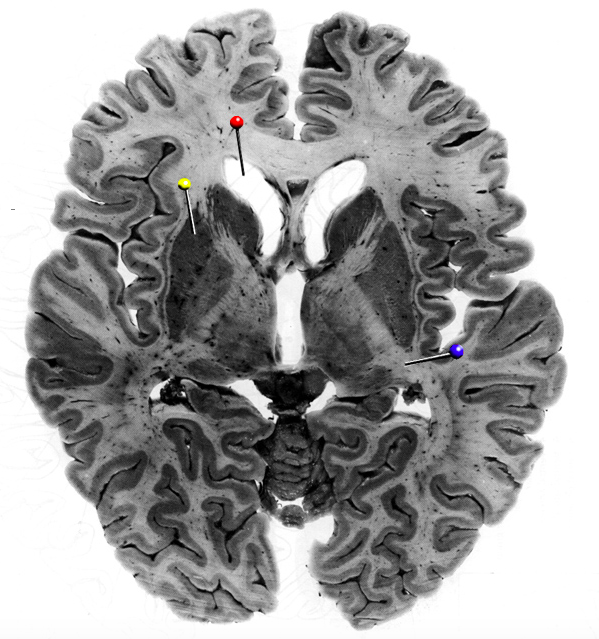

In this horizontal brain slice, the yellow pin is in

In this horizontal brain slice, the yellow pin is in the…

putamen

What is the structure indicated by the black pin?

?

What fibres is the structure marked by the black pin made up of?

Commisural fibres